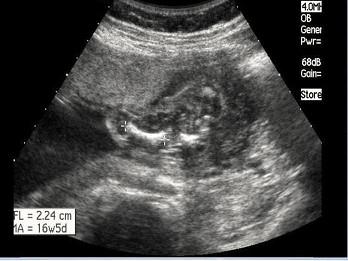

问题 24周胎儿股骨超声检查如图,最可能的诊断是?(?)

选项 A.致死性骨发育不全 B.内翻足 C.羊膜带综合征 D.骨硬化症 E.并指(趾)畸形

答案 A